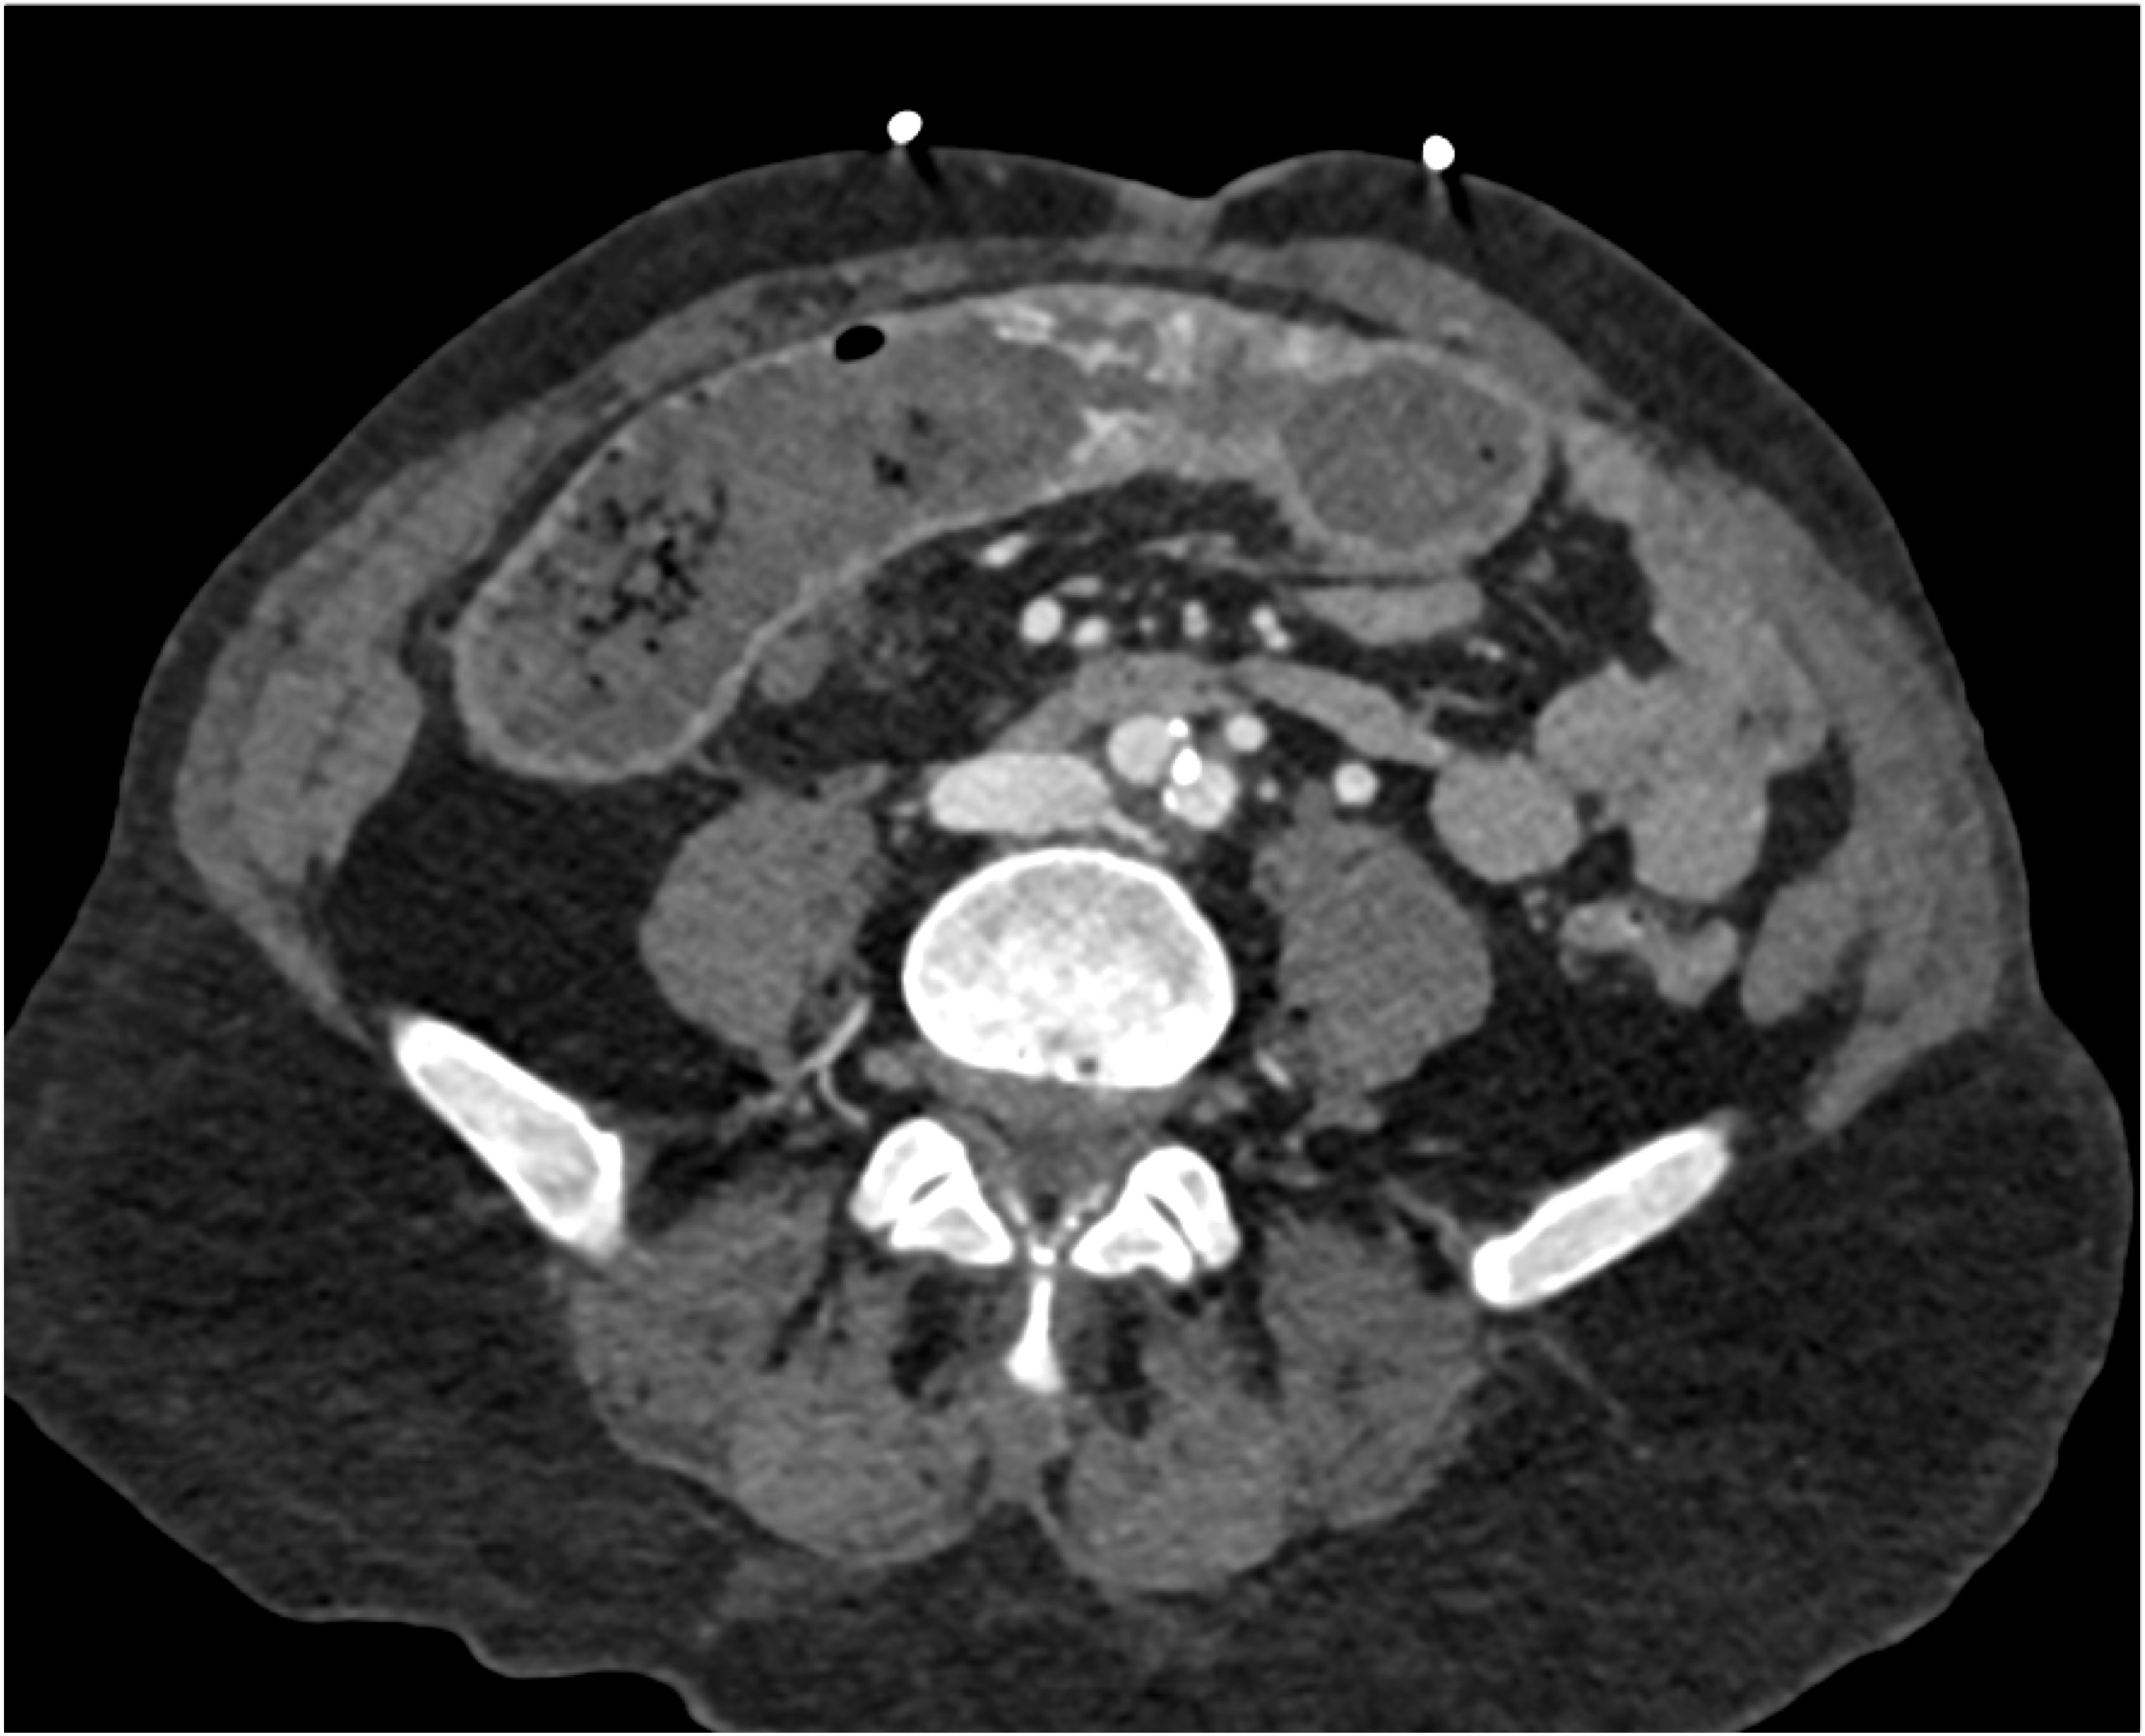

2) In this patient with a palpable right abdominal wall mass the best dx is?

rectus sheath hematoma

lymphoma

desmoid tumor

metastatic renal cell carcinoma